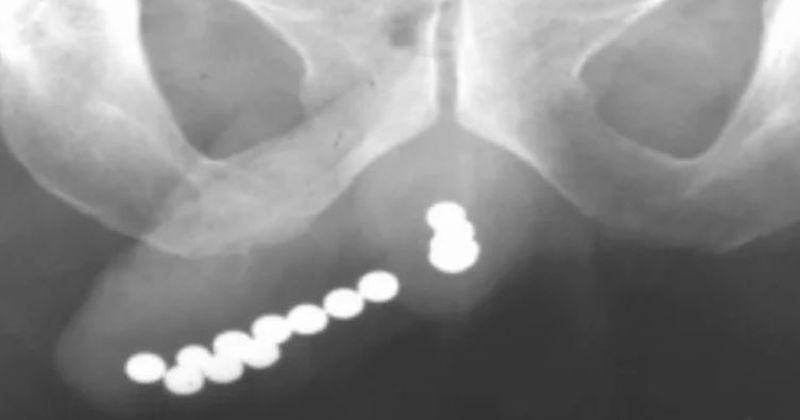

Sedang Puber, 39 Biji Magnet Ditemukan Masuk ke Penis Bocah 12 Tahun

Bocah laki-laki asal Tiongkok baru saja menjalankan operasi besar setelah diketahui ginjalnya berhenti memproduksi urine. Setelah diselidiki, ternyata penyebabnya adalah benda asing yang sengaja dimasukkan ke dalam penisnya.

Insiden yang mengkhawatirkan itu terjadi pada (13/01). Menurut laporan berita, orangtua dari anak yang tidak disebutkan namanya itu merasa khawatir ketika anaknya menunjukkan gejala anuria atau tidak bisa buang air kecil.

Mengetahui hal tersebut, sontak orangtuanya pun segera membawanya ke rumah sakit. Awalnya, bocah 12 tahun tersebut mengeluh sakit perut dan mengatakan bahwa ia telah menelan biji magnet.

Namun, ahli urologi menemukan bahwa 39 biji magnet tersebut telah sengaja dimasukan ke dalam saluran kemihnya. Akhirnya bocah itu pun mengaku bahwa ia telah memasukan biji magnet tersebut ke dalam penisnya karena penasaran.

Dokter mengatakan bahwa mereka telah menemukan banyak kasus benda asing yang tersangkut di uretra, terutama di kalangan anak laki-laki berusia 11-12 tahun, yang baru saja mencapai masa puber.

Untungnya, dalam kasus ini, dokter berhasil mengeluarkan biji magnet melalui proses operasi, dan akhirnya anak-anak tersebut dapat buang air kecil kembali seperti sedia kala.